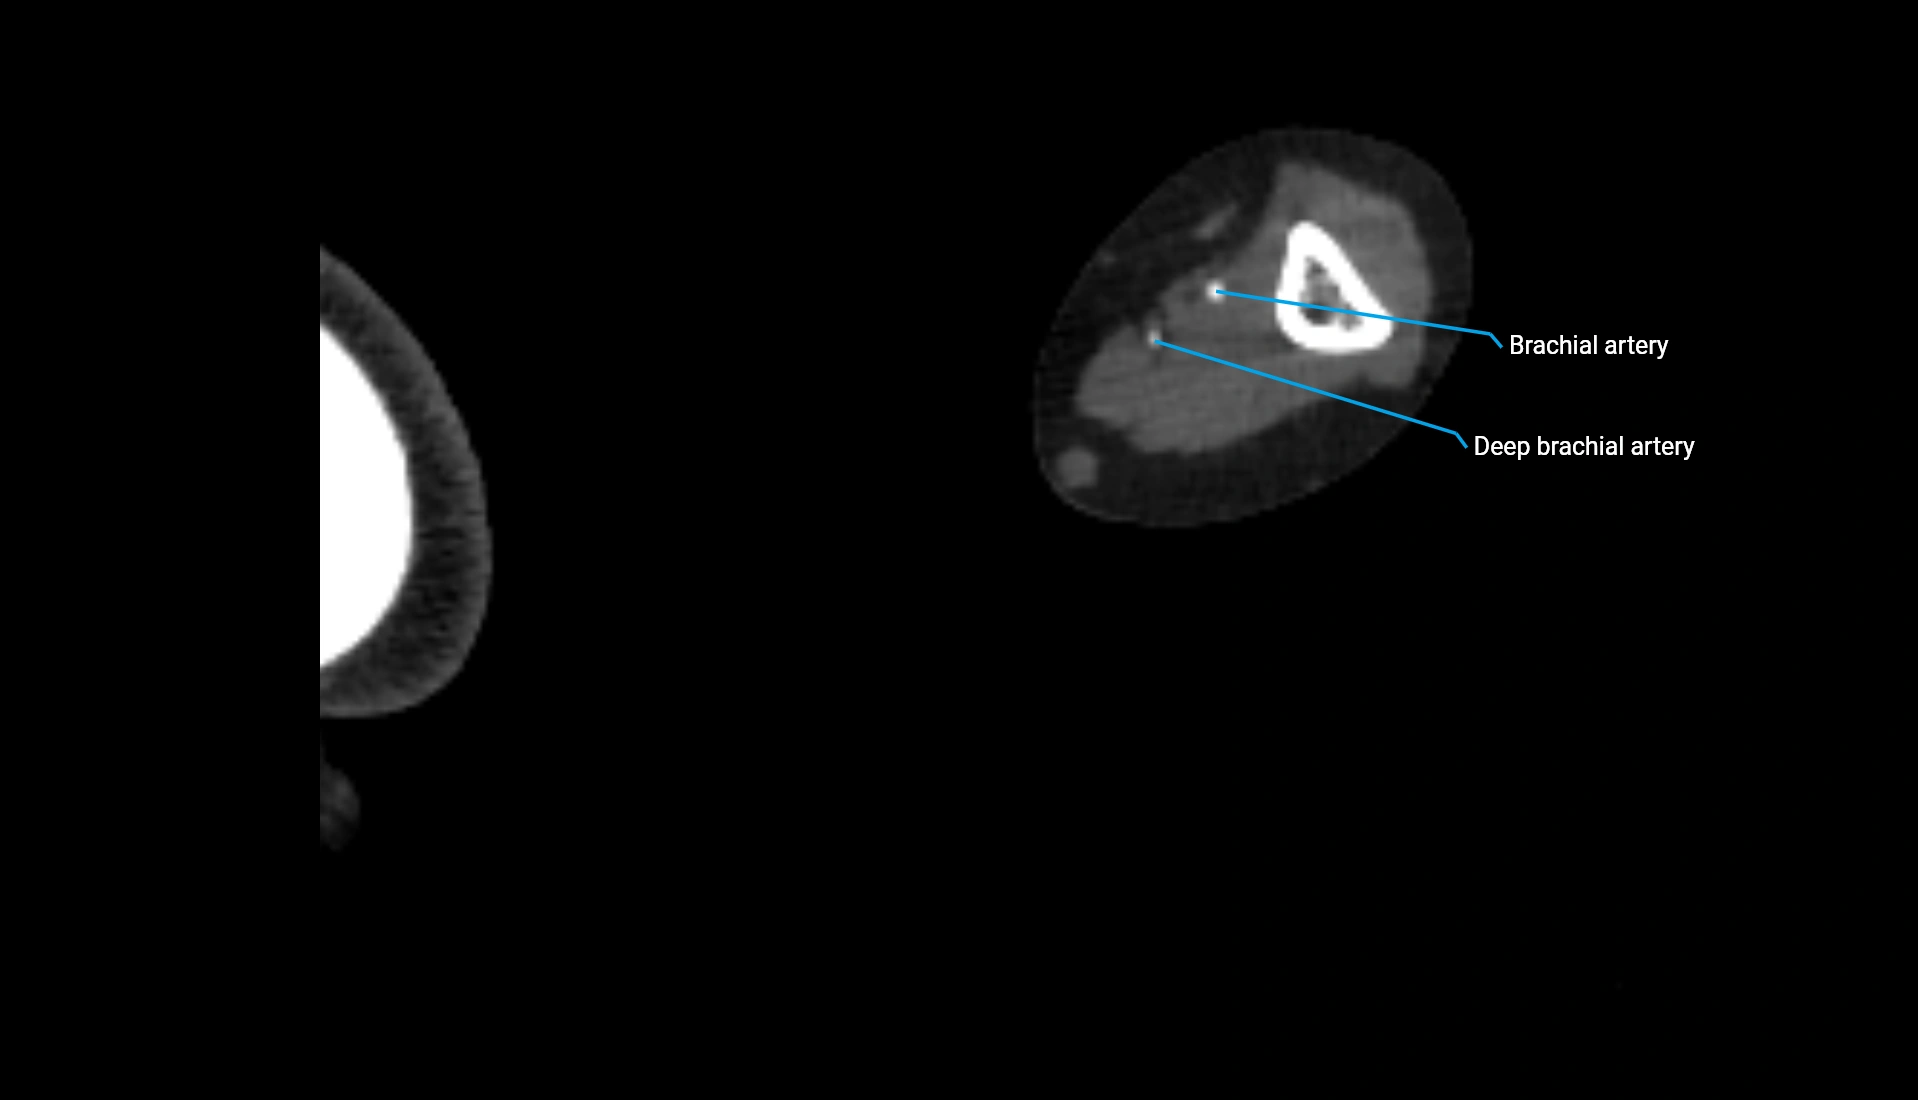

CT Appearance

Non-Contrast CT:

• Cortex: High-density, sharply defined

• Subchondral bone: Dense cancellous matrix

• Articular surface: Smooth concave contour articulating with the capitellum

• Excellent for evaluating bone integrity, alignment, and subtle fractures